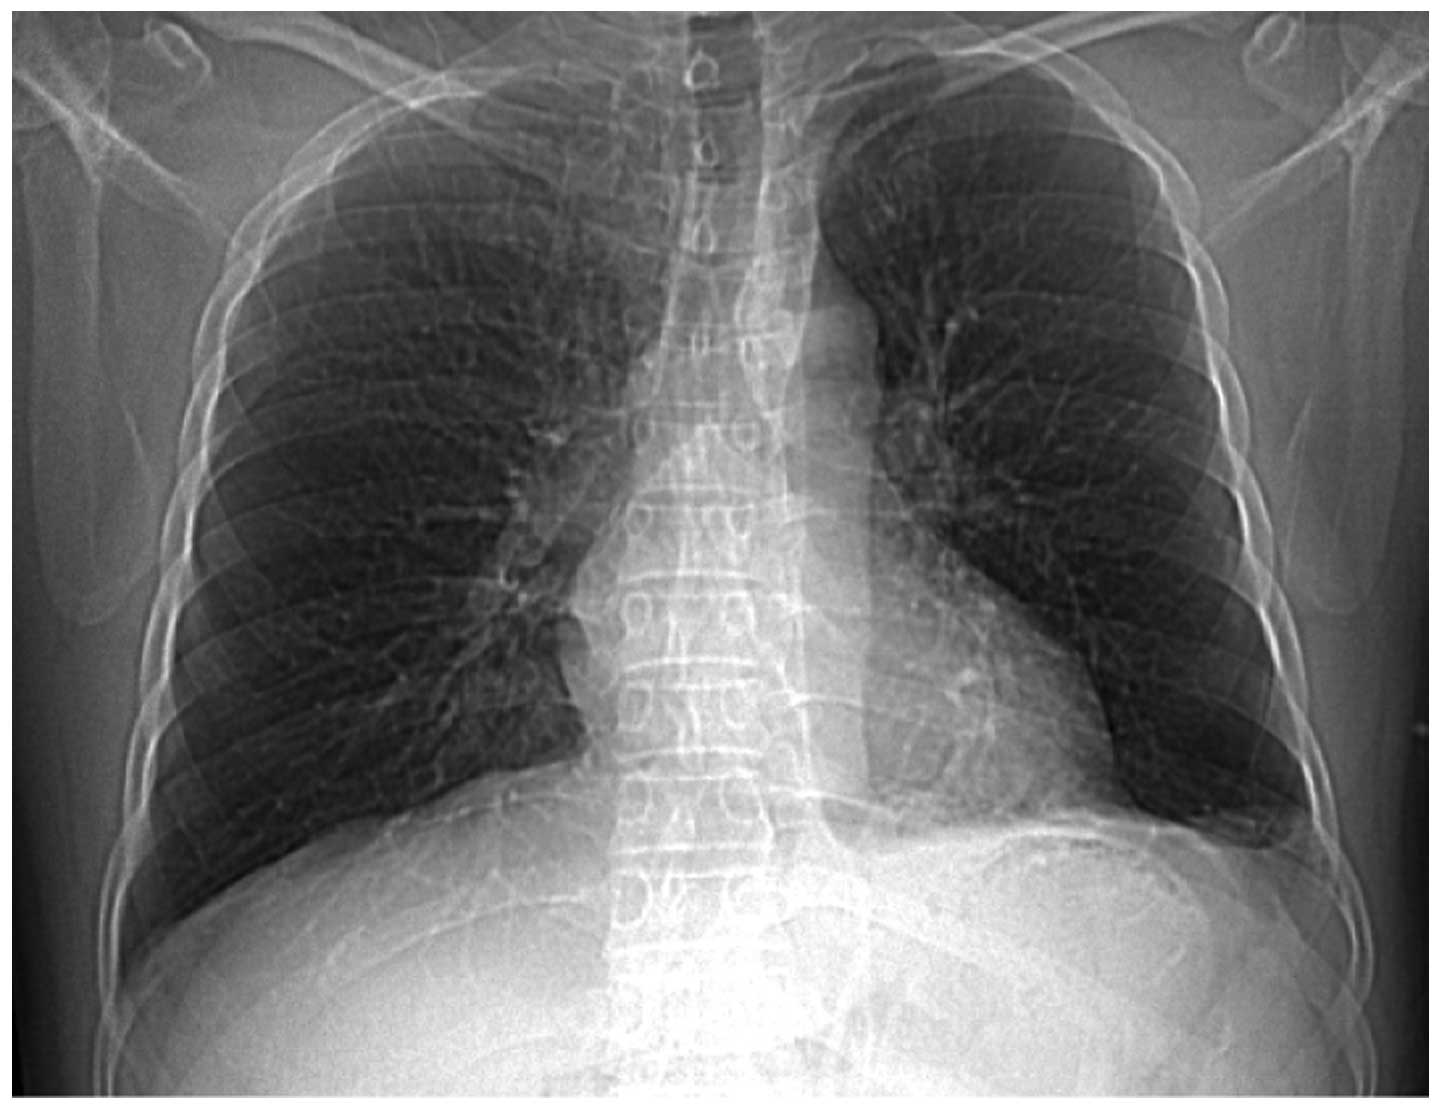

The patient was a non-smoker and had no family history of pulmonary tuberculosis (TB) or bronchiectasis. However, the patient had pneumonia in 2009, which was cured following antibiotic treatment. The physical examination showed no abnormalities and the laboratory examination revealed a marginal increase in serum γ-guanosine triphosphate (80 IU/l) and serum CA19-9 levels increased to 1,242.85 U/ml. To exclude the possibility of an underlying abnormal malignant lesion, esophagogastroduodenoscopy, endoscopic ultrasonography, colonoscopy, abdominal ultrasonography and computed tomography (CT) were performed with no specific abnormalities identified. A chest X-ray that was performed on admission of the patient to hospital showed a dense shadow cord strip in the left lower region (Fig. 1). In addition, chest high-resolution CT scanning and 3D image reconstruction further indicated anomalous arteries arising from the descending thoracic aorta (Fig. 2). Pulmonary sequestration was diagnosed, and surgery confirmed the presence of two aberrant arteries arising from the thoracic aorta and entering the left lower lobe basal segment. The sequestrated lung was consolidated and tightly connected to the diaphragm (Fig. 3). A left lower lobectomy was performed and the postoperative pathological observations were consistent with intralobar pulmonary sequestration. Immunohistochemistry staining using a monoclonal antibody against human CA19-9 (Maixin Biotechnology, Fuzhou, China) demonstrated marked positive staining for CA19-9 in the ciliated cylindrical epithelia, alveoli and particularly in the mucus of the cysts (Fig. 4). Following pulmonary resection, the symptom of bloating improved and the serum CA19-9 levels rapidly decreased to within the normal range (34.5 U/ml; Fig. 5).

Figure 1

Chest X-ray film on admission showed a dense shadow cord strip in the left lower region.